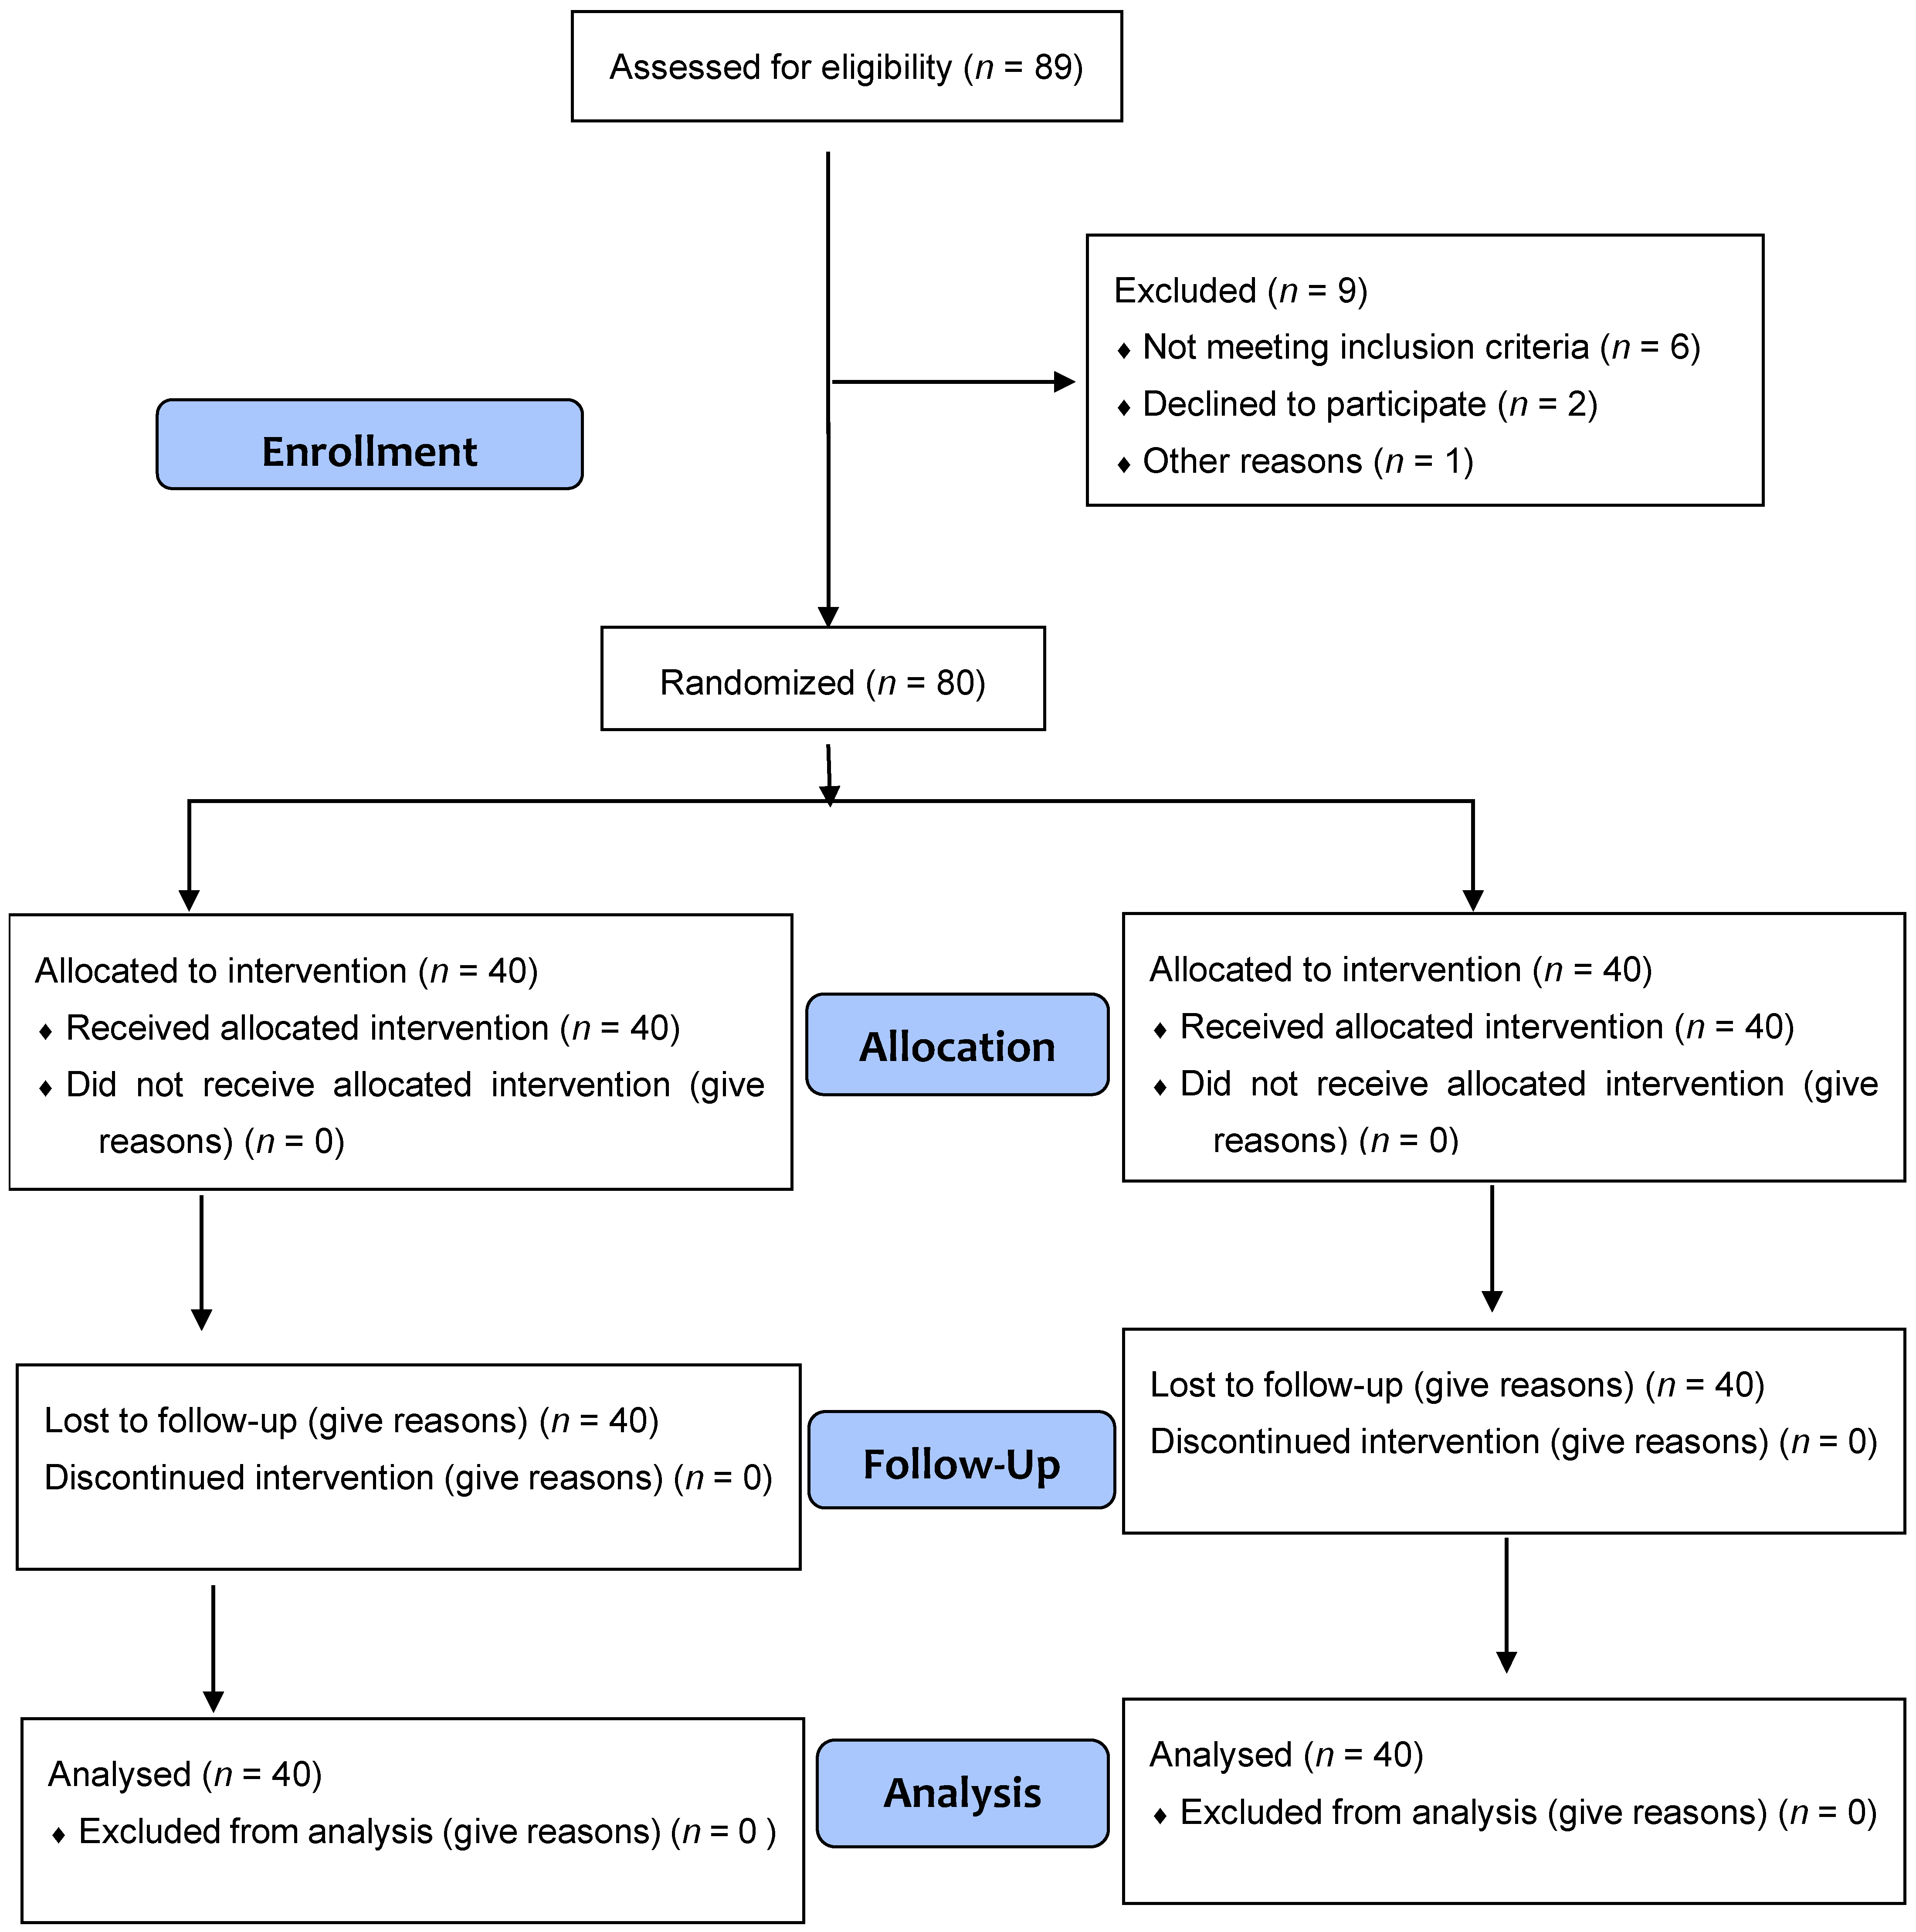

2. Materials and Methods